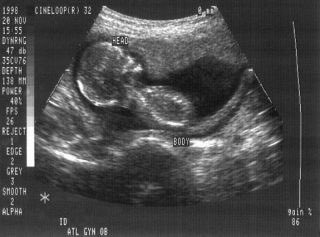

أحد الوسائل الشهيرة لمعرفة جنس الجنين بداخل رحم الأم هي استخدام Ultrasound Imaging والتي تستعمل تقنية Ultrasonic (الموجات فوق الصوتية) لتصوير ما بداخل الجسم، دعونا نتعرف على تقنية Ultrasonic باختصار.

٢- التصوير الصوتي (Ultrasound imaging)

والذي تحدثنا عنه في أول تغريدة ، حيث يقوم بإطلاق الموجات بداخل جسم الإنسان وباختلاف سرعة انتشار الصوت لأعضاء الإنسان تختلف الصور التي تظهر على الشاشة على حسب العضو، لكن بالطبع لا يستعمل ذلك الحساس البسيط والمعروف، بل يستعمل حساس معقد جدا.